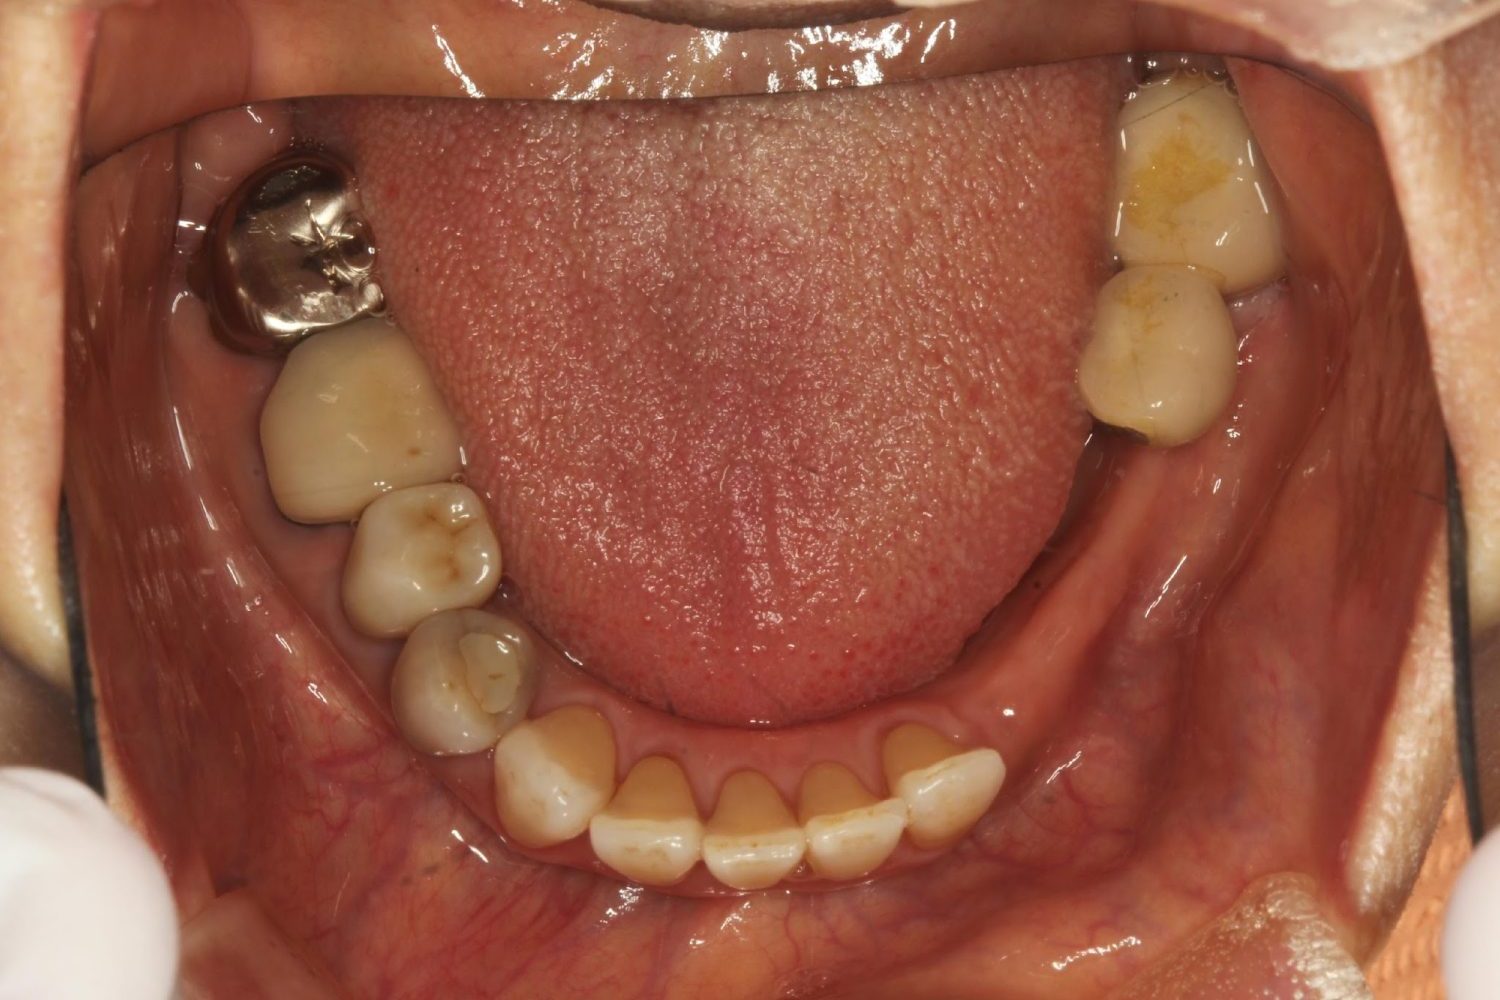

インプラント治療の症例紹介③

Before

After

主訴

むし歯の治療

治療内容

保存不可能な歯の抜歯

下顎にインプラント埋入し咬合再構成

治療費

2,688,400円(税込)

治療期間

14か月

治療回数

21回

想定されたリスク

※上部構造の形態が複雑になるため清掃が難しくなる。インプラント周囲炎の恐れがありました。

多数歯う蝕および多数歯欠損による咬合崩壊、保存不可能な歯の抜歯により上下無歯顎に。下顎に6本インプラント埋入する事で咬合再構成を行った。